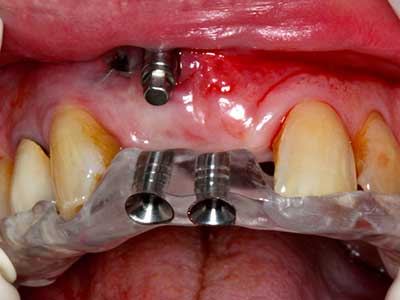

Фиг. 16: Интраоралните условия също са стабилни с поставените импланти в кератизираната гингива.

Фиг. 14: Поставяне на RSX имапланта (Bego Implant Systems, Bremen).

Фиг. 13: Подходяща иригация с остатъчна 4 mm дебелина на костта е важна за този 52-годишен пациент по време на разделянето на костта.